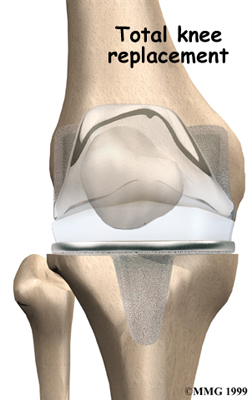

Artificial Knee Replacement

An artificial knee replacement is the ultimate solution for advanced knee OA.

Surgeons prefer not to put a new knee joint in patients younger than 60. This is because younger patients are generally more active and might put too much stress on the joint, causing it to loosen or even crack. A revision surgery to replace a damaged prosthesis is harder to do, has more possible complications, and is usually less successful than a first-time joint replacement surgery.

Related Document: FYZICAL Stone Oak's Guide to Artificial Joint Replacement of the Knee